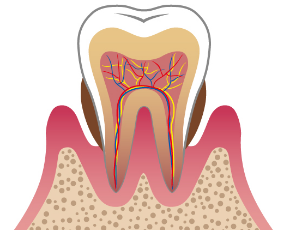

むし歯とは、お口の中のむし歯の原因菌が糖分を分解してネバネバになり、歯に付着してから、そこで「酸」を出し、その「酸」が歯の成分を溶かしていく病気です。ごく初期の段階を「脱灰(だっかい)」といいます。それは歯の表面のエナメル質の成分が溶け出す状態ですが、この場合は、「再石灰化(さいせっかいか)」で元に戻ります。しかし、その段階を過ぎると、むし歯はどんどん進行し自然には治りません。放っておくと歯の中の神経にまで汚染がおよび、やがては歯を失うことにもつながるのです。

C3:歯の中の神経にまでおよんだむし歯

症状

象牙質の内側の歯の神経にまで汚染が進んだ状態です。何もしなくてもズキズキ痛みます。

主な治療法

できるだけ歯残すために、神経や血管を取り除いて薬剤をすき間なく詰める「根管治療(こんかんちりょう)」を行い、被せ物で歯の機能を補います。

根管治療

根管治療とは、おおまかにいうと歯の根の中を通る神経の治療のことを指します。

むし歯がかなり進行していると、むし歯菌が歯の神経まで到達してしまうことがあります。

多くのケースでかなりの痛みを伴うことがほとんどなので、こうなってしまった場合は痛んだ神経を取り除き、なおかつ歯の根の中をきれいに洗浄し、薬を詰める必要があります。この治療工程を、根管治療といいます。

この根管治療ですが、非常に難しい治療です。

歯の根の中は直接肉眼で見ることが不可能な上に、歯の神経が通っている管は細く、複雑に枝分かれしているからです。